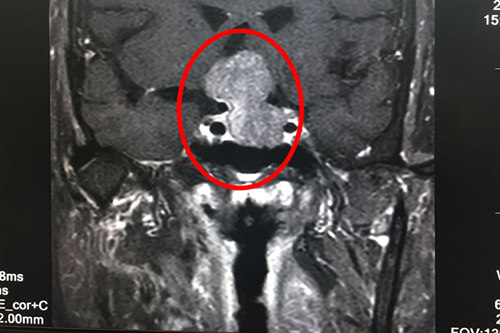

术前核磁共振显示:垂体巨大腺瘤(画圈部分)